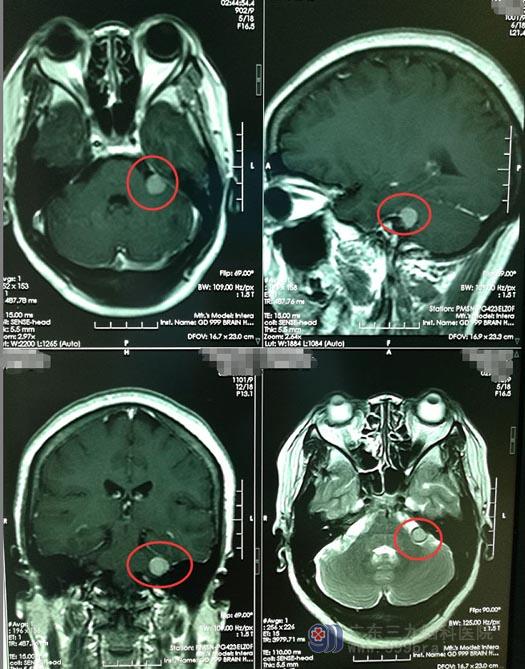

不久前,郑阿姨在家中打扫卫生时不慎撞到头部,当时就有头痛,立即到当地医院检查,头颅MR发现“左侧桥小脑角占位性病变,考虑脑膜瘤”。

她的家人虽然有担心,但是对于战胜疾病还是充满了信心,带着郑阿姨来到了广东三九脑科医院神经外五科。头颅CTA示:1.左侧桥小脑角区占位性病变血供较丰富,周缘可见血管影缠绕,考虑脑膜瘤可能性大;2.颈部及脑动脉轻度硬化;3.右侧胚胎型大脑后动脉,考虑发育因素所致。

▲手术前